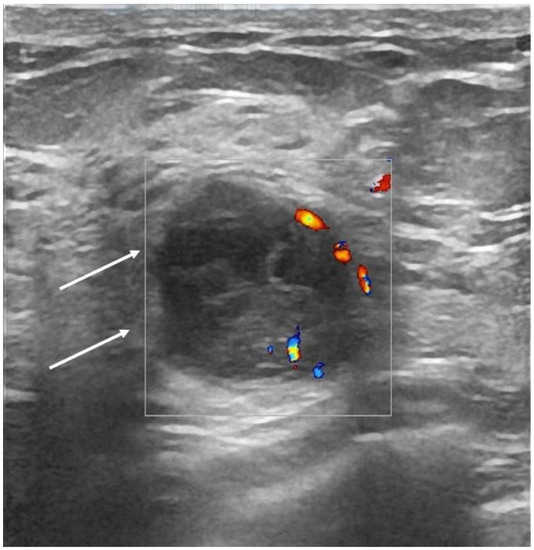

| Echo pattern | 0.000 | ||

| Hypoechoic | 57 (58.2) | 100 (70) | |

| Heterogeneous | 36 (36.7) | 19 (13) | |

| Isoechoic | 5 (5.1) | 26 (17) | |

| Posterior features | 0.000 | ||

| None | 39 (39.8) | 71 (49) | |

| Enhancement | 27 (27.6) | 12 (8.3) | |

| Shadowing | 15 (15.3) | 54 (37.2) | |

| Combined | 17 (17.3) | 8 (5.5) | |

| Strain Elastography | 0.029 | ||

| Soft | 40 (40), 9 BGR | 30 (20.6), 1 BGR | |

| Hard | 58 (60) | 115 (79.3) | |